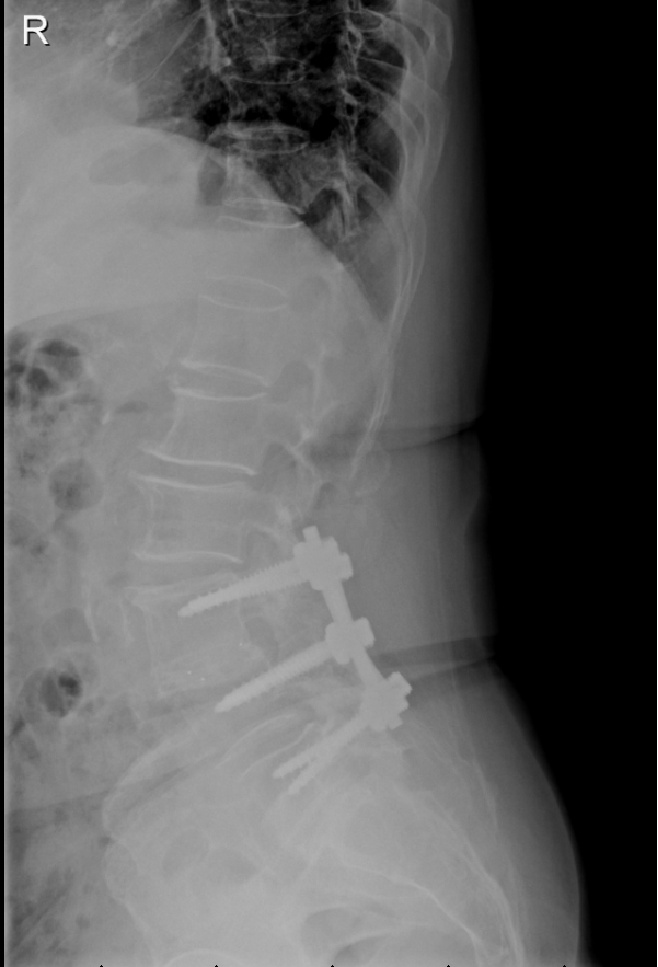

术前X-RAY显示严重脊柱侧弯,椎管内肿瘤

“这种情况,常规会进行开放手术,治疗刀口有20公分左右,脊柱内需要置入10-12枚螺钉,对于高龄、体弱的病人,存在创伤大、出血多、恢复慢等缺点。”曹鹏医生介绍,若单纯做脊柱肿瘤切除,患者已经侧弯的脊柱会加重,严重影响患者预后康复。